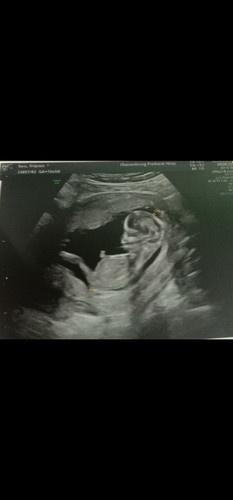

เพศไหนเอ่ย

เห็นน้องชัดมากค่ะตอนซาว13สัปดาห์เองค่ะอยากรู้ว่าจะทราบเพศไหมค่ะ

รออายุครรภ์มากกว่านี้หน่อย ค่อยซาวด์เพศดูนะคะ หรือไม่ก็ถามหมอก็ได้ว่ากี่เดือนถึงอัลตร้าซาวด์เพศได้